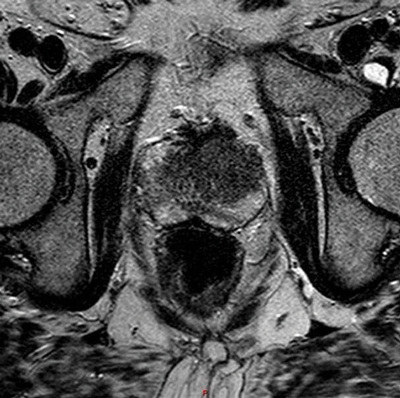

Although MR is most accurate in the detection of peripheral zone tumours, central / transitional zone tumours should also be actively considered, especially in patients with rising PSA and multiple negative transrectal biopsies [2]. Given the commonly heterogeneous appearance of the central gland, MR interpretation may be difficult, but the presence of the following may aid diagnosis: homogenous low signal intensity in the central zone (especially in the absence of an obvious peripheral zone tumour), poorly defined or speculated margins, absence or interruption of the low-signal pseudocapsule or urethral invasion (Figure 4) [2].

Figure 4: Axial T2 image showing diffuse low signal in the left central zone.